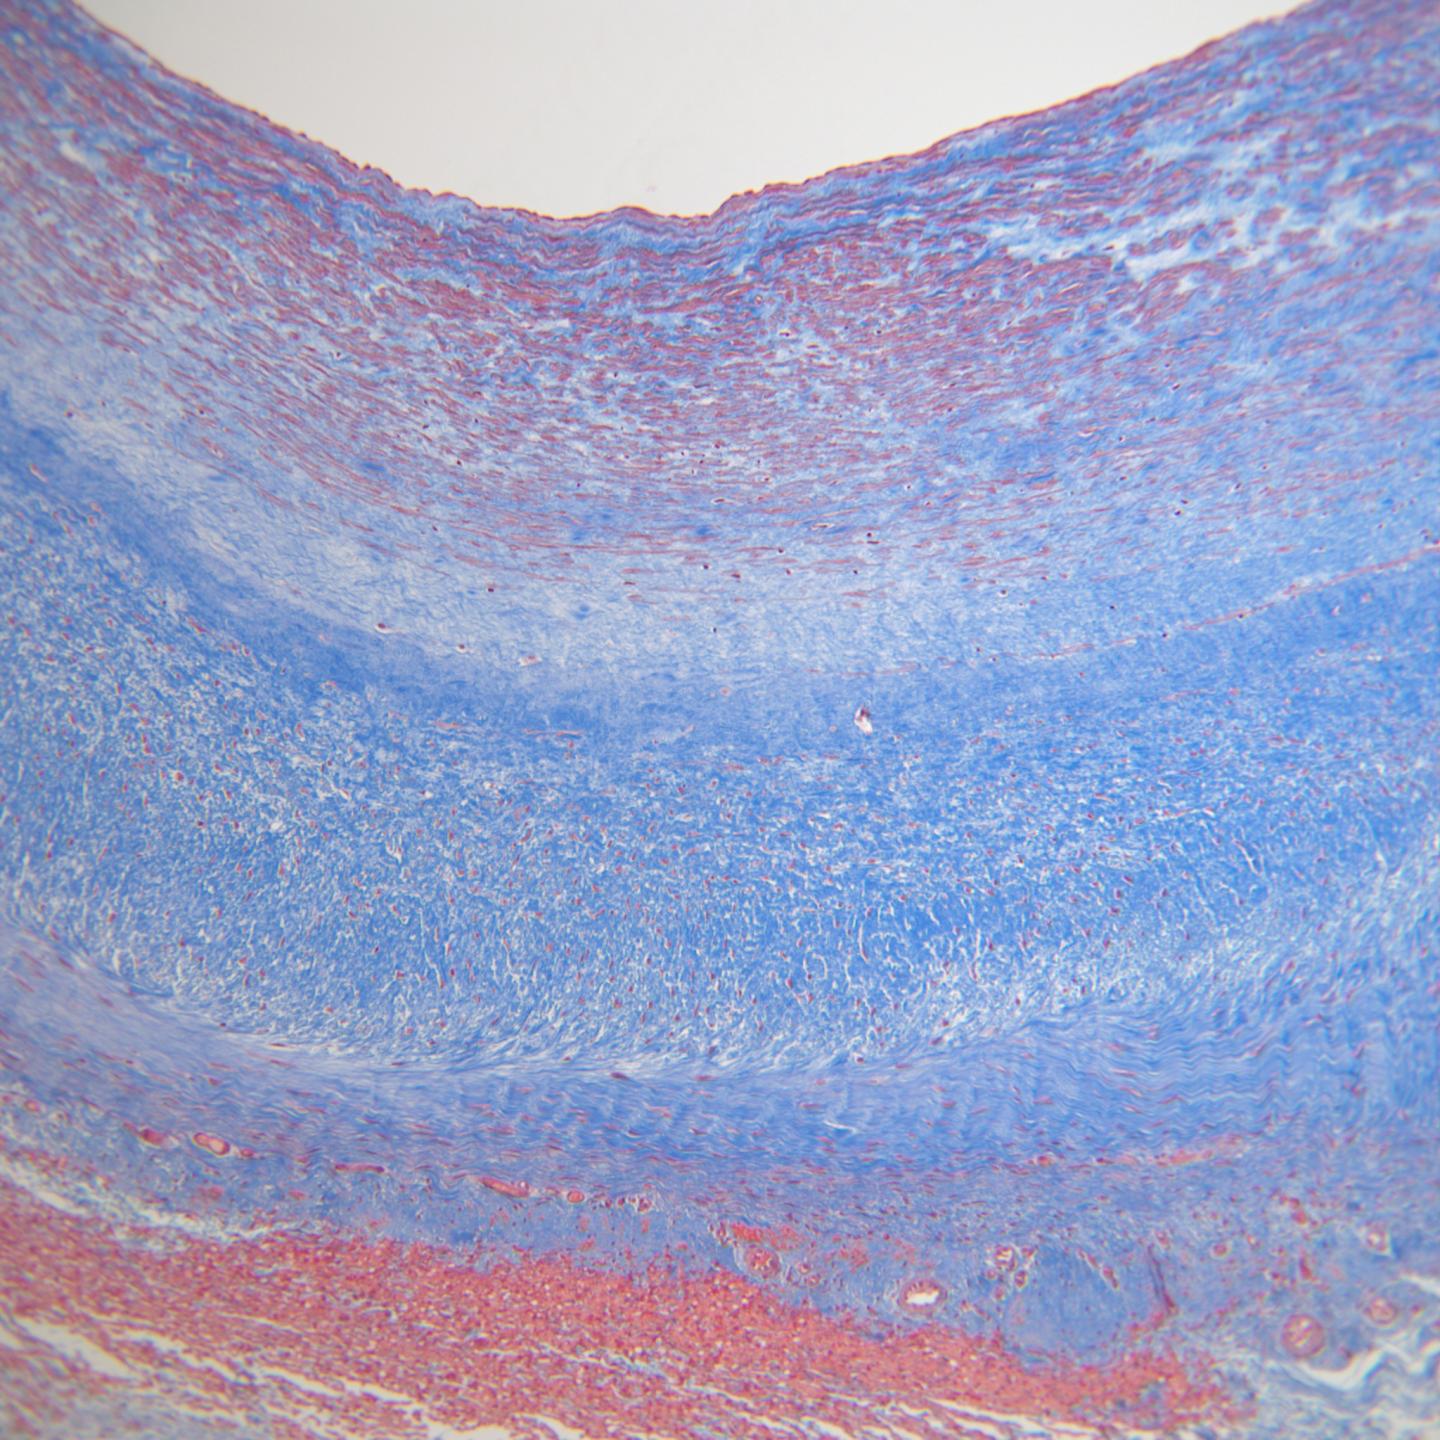

In this pre-clinical study, University of Minnesota researchers generated vessel-like tubes in the lab from post-natal human skin cells that were embedded in a gel-like material made of cow fibrin, a protein involved in blood clotting. Researchers put the cell-populated gel in a bioreactor and grew the tube for seven weeks and then washed away the cells over the final week. What remained was the collagen and other proteins secreted by the cells, making an all-natural, but non-living tube for implantation.

To test the vessels, the researchers implanted the 15-centimeter-long (about 5 inches) lab-grown grafts into adult baboons donated by Mayo Clinic as it was closing down its primate facility. Six months after implantation, the grafts grossly appeared like a blood vessel and the researchers observed healthy cells from the recipients taking up residence within the walls of the tubes. None of the grafts calcified and only one ruptured, which was attributed to inadvertent mechanical damage with handling. The grafts after six months were shown to withstand almost 30 times the average human blood pressure without bursting. The implants showed no immune response and resisted infection. In addition, the grafts withstood repeated needle punctures by self-healing, which would be a necessary process for patients undergoing long-term dialysis.